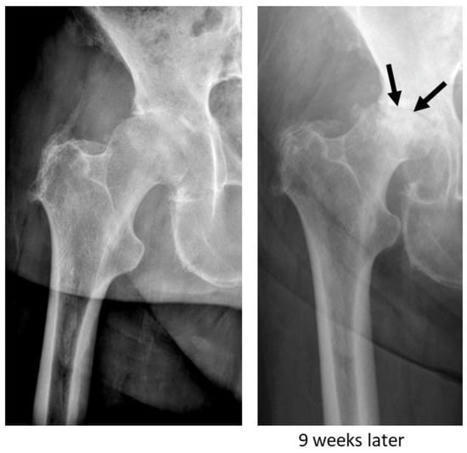

Background: Rapidly destructive osteoarthritis (RDO) of the hip joint is characterised by the rapid destruction of the femoral head with or without acetabular involvement. There has been increasing interest in this disease over the past years; however, the entity is still poorly understood, and...